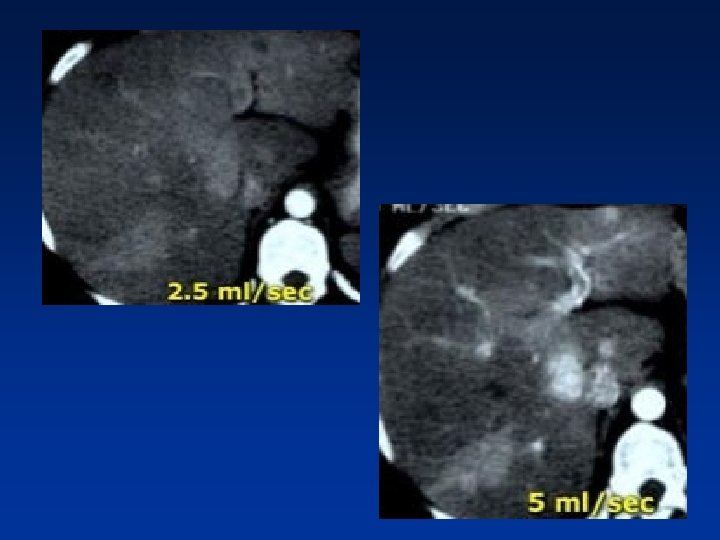

For arterial phase the best results are with an injection of 5 ml/sec

• Patient with liver cirrhosis and multifocal HCC injected at 2. 5 ml/sec and at 5 ml/sec. • At 5 ml/sec. there is far better contrast enhancement and better tumor detection.